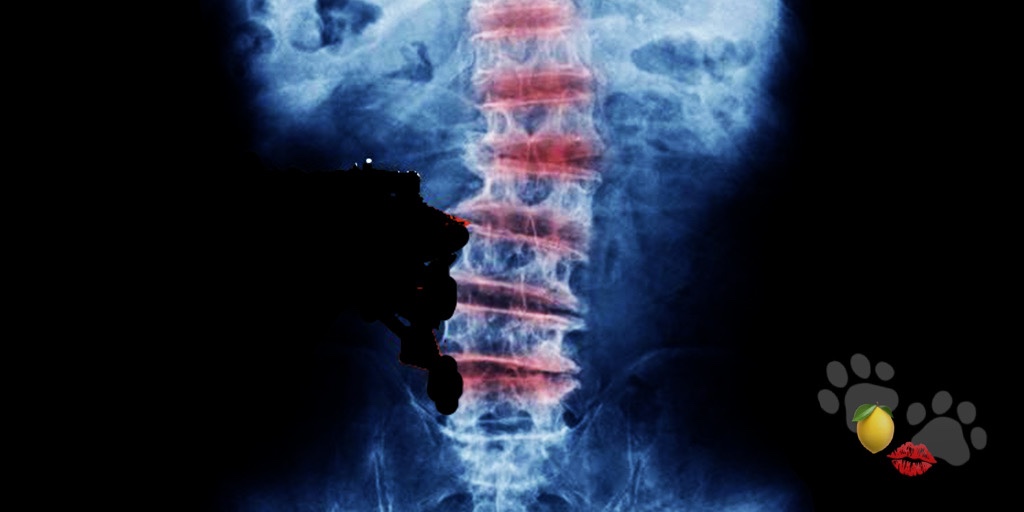

Degenerative Disc Disease (DDD; Spinal osteoarthritis) is an incurable genetically passed disorder.

DDD occurs when the cartilage spaces in-between the sectional vertebrae in the spine dissipate at an arthritic rate.

My DDD was so severe after years of neglect and carrying three children to term weighing 8 pounds or more- my body had started to break down.

One year and 8 days later, it happened. My first experience with temporary paralysis. My lower spine had become so degraded, without the surgery to repair the damaged spaces… I was slated to be wheelchair bound.

I officially started my transition to Robo-Copism with the reinforcement of my spine.